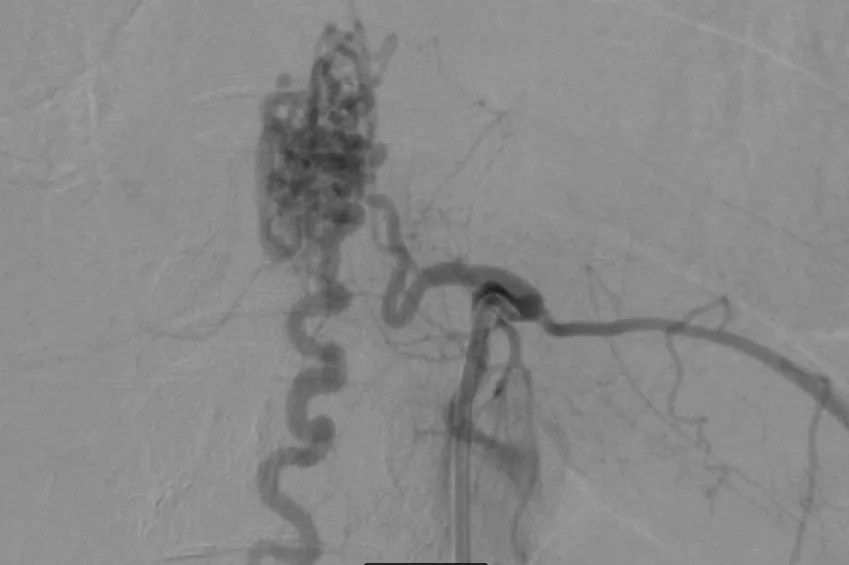

Kết quả chụp MRI cho thấy chị S. bị dị dạng mạch máu tủy sống. Ảnh: BVCC

Chị S. được điều trị bằng kỹ thuật đưa ống thông siêu nhỏ để tiếp cận ổ dị dạng, đồng thời bơm keo sinh học để tắc ổ dị dạng. Sau 3 tiếng, các bác sĩ (BS) loại bỏ được khối dị dạng, bảo tồn các chức năng thần kinh, đặc biệt chức năng vận động. Hiện chị S. có thể tự đứng và đi lại nhẹ nhàng. Sau khi xuất viện, chị S. tiếp tục tập vật lý trị liệu phục hồi chức năng.

BS Phạm Định Chương, khoa Nội thần kinh BV Hoàn Mỹ Sài Gòn, cho biết chị S. rơi vào bệnh lý hiếm gặp. Đặc biệt, chị có nguy cơ liệt 2 chân kèm rối loạn tiêu tiểu nếu tắc động mạch lành nuôi tủy. Do đó, các BS buộc sử dụng phương pháp loại bỏ khối dị dạng nhưng phải bảo tồn các động mạch nuôi tủy.